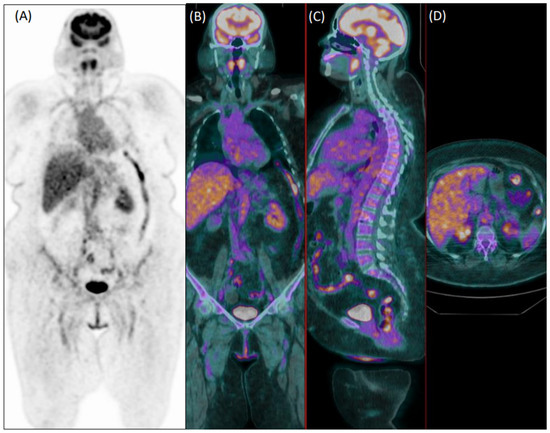

In total, 81 patients (29%) were clinically diagnosed with LVV. Reader 1 and reader 2 failed diagnosis in 76 patients (37 false negative and 39 false positive) and 92 patients, respectively (33 false negative and 59 false positive). Figure 1 and Figure 2 show examples of a true positive and a false positive PET exam. Among the 76 patients wrongly classified by reader 1, 51 were >65-years-old, 44 were overweight, 46 were taking steroids, 12 presented with hyperglycemia, 29 were early acquired, while in 26 patients, the acquisition was delayed, and 23 were scanned with P1.

Figure 1. Coronal [18F]FDG PET (A) and fused PET/CT coronal (B), sagittal (C) and axial (D) images of an 80-year-old male patient with fever of unknown origin. Images show diffuse increased uptake in the abdominal aorta, common iliac, and femoral arteries. Both readers evaluated this exam as positive for vasculitis, which was confirmed during clinical follow-up.